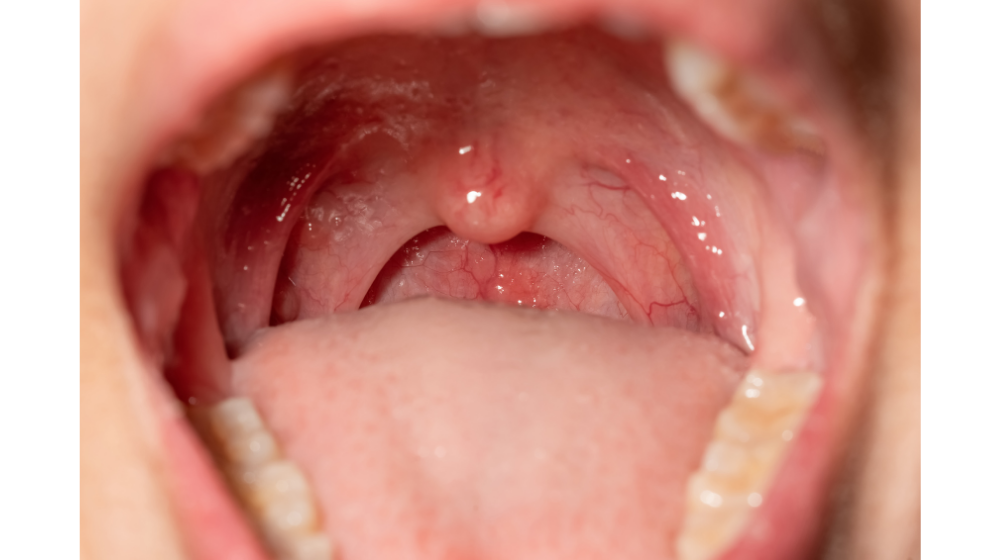

ヘルパンギーナ 写真 画像 (350 無料画像)

ヘルパンギーナ 写真 画像